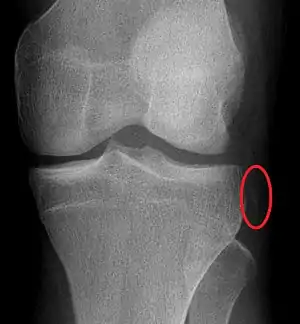

| Plain lateral X-ray of the left knee showing a posterior knee dislocation[1] | |

Plain X-rays, CT scan, ultrasonography, or MRI may help with the diagnosis.[2][11] Findings on X-ray that may be useful among those who have already reduced include a variable joint space, subluxation of the joint, or a Segond fracture.[5]